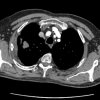

71 male First appointment 3 Month history of Right rhomboid pain. Aggravated by shoulder movements. Struggles to get to sleep and occasionally wakes up. No P+N or numbness. No dizziness, diplopia, dysarthria, dysphagia, drop attacks, nausea. Exam Slight winging right scapula. Full shoulder ROM Full shoulder strength Provisional Diagnosis [...] Read more